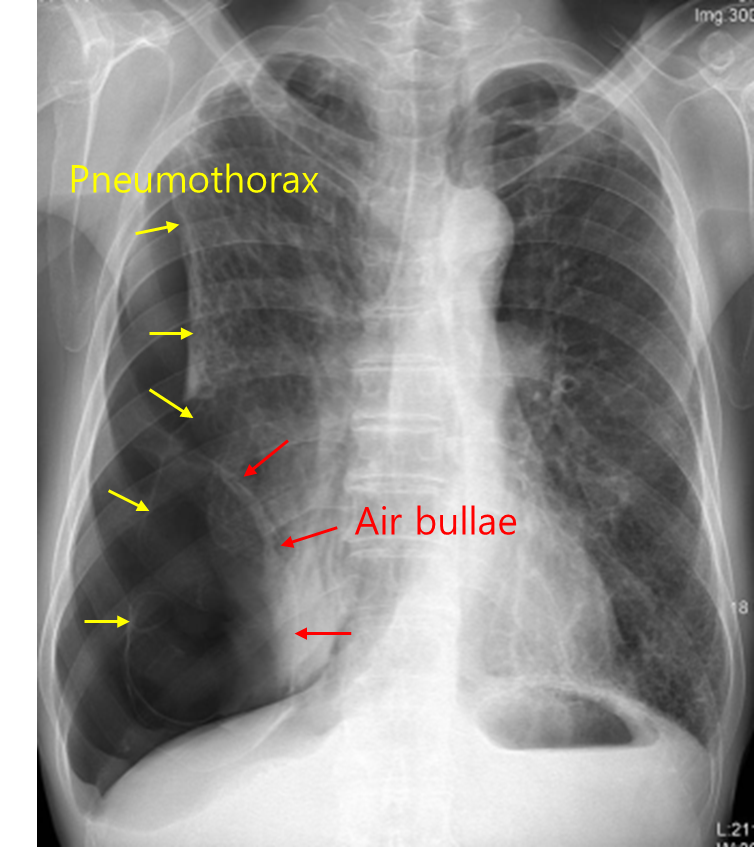

70세 남자가 3일 전부터 숨이 차서 병원에 왔다. 3일 전에 가슴이 아팠었고, 점점 숨쉬기가 어려워졌다고 한다. 50갑·년의 흡연자이고, 7년 전부터 기관지확장제를 흡입 중이다. 혈압 150/85 mmHg, 맥박 126회/분, 호흡 28회/분, 체온 37.0℃이다. 오른쪽 가슴에서 호흡음이 들리지 않는다. 가슴 X선 사진이다. 적절한 치료를 고르시오(한 가지).

Img | CXR: hyperinflation, flattened hemidiaphragm, right pleural line |

Imp: 이차성 자발성 기흉(secondary spontaneous pneumothorax, SSP)

COPD에 의한 이차성 기흉이 의심되므로 1차 치료로 흉관 삽입을 한다.

• 장기간의 흡연력이 있고 CXR에서 과다팽창, 횡경막 평평이 있으므로 기관지확장제는 COPD 치료로 흡입하고 있었던 것으로 생각된다.

• 오른쪽 가슴에서 호흡음이 들리지 않고 CXR에서 우측 폐야에 visceral pleural line이 보이므로 COPD에 의한 이차성 기흉이 의심된다.

• 따라서 이차성 기흉의 치료로 가슴관 삽입을 한다.